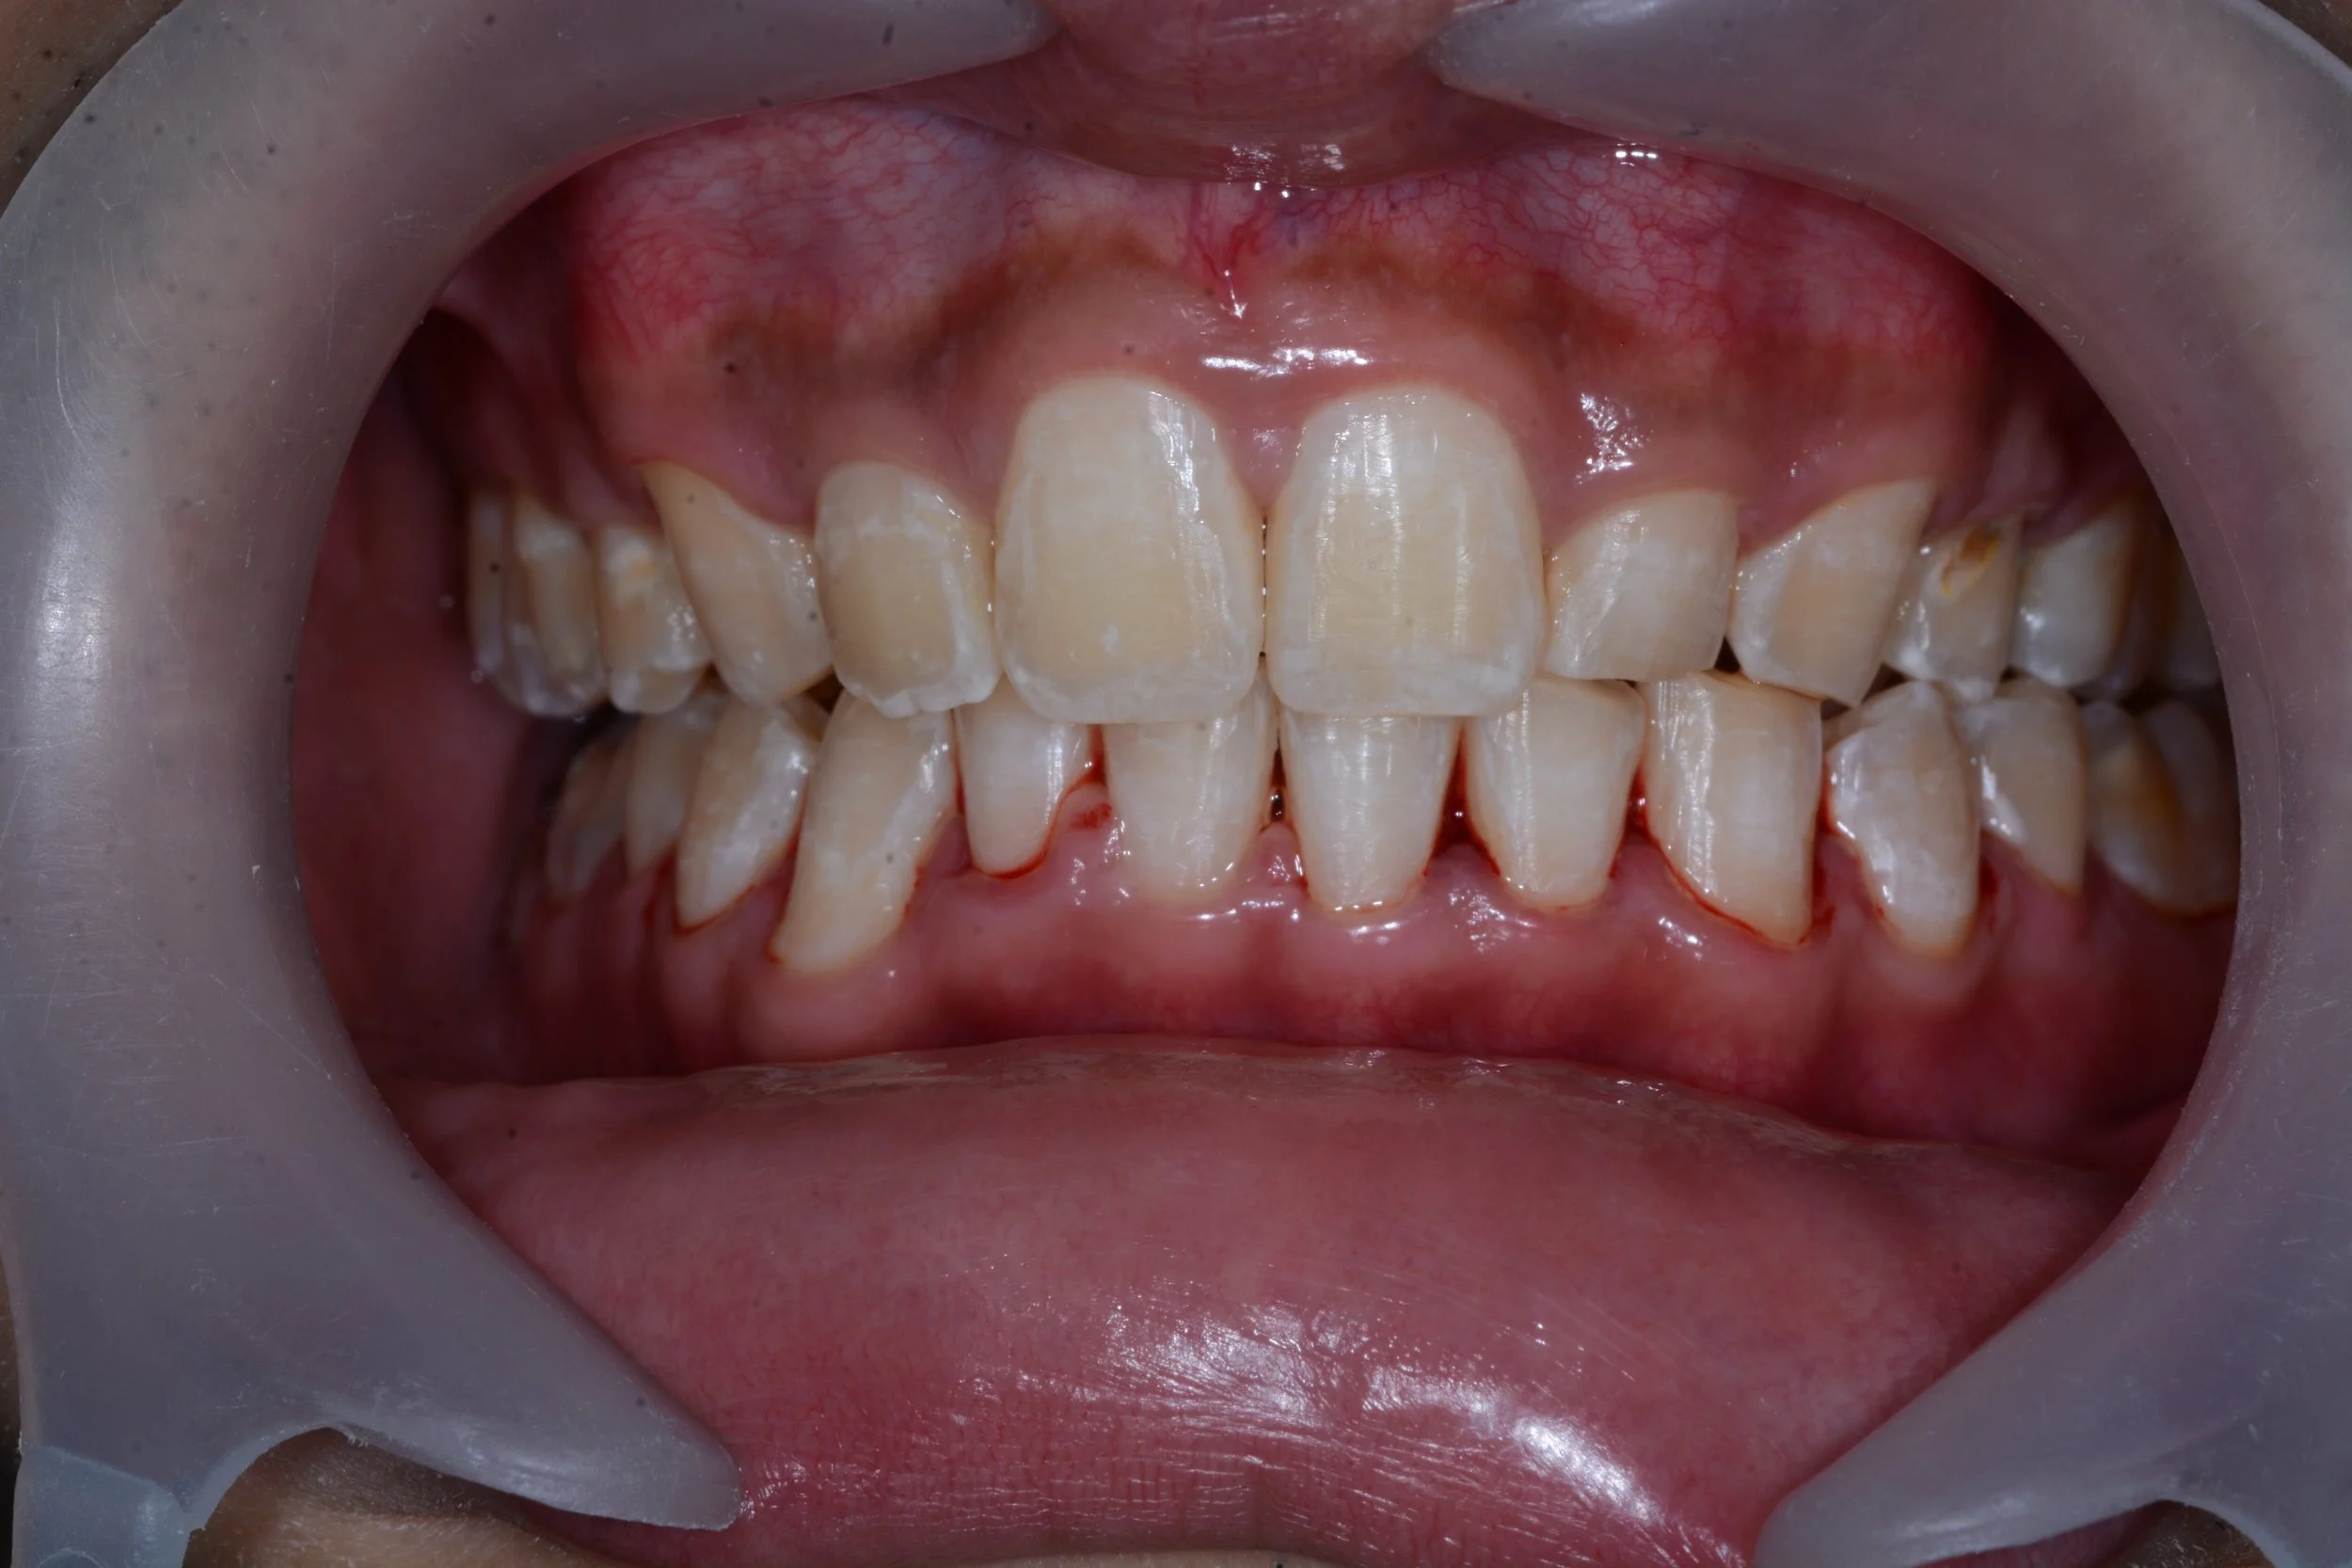

DSC_1041.JPG

DSC_1011.JPG

BEFORE

SINGLE FRONT TOOTH IMPLANT